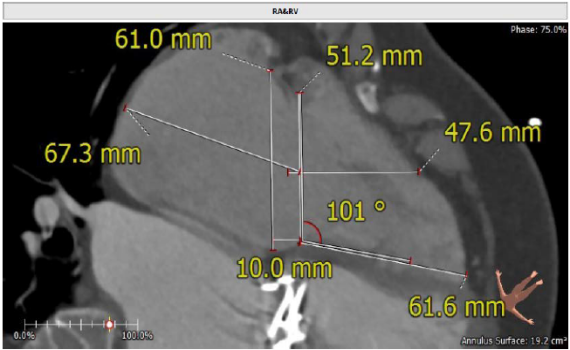

术前CT评估